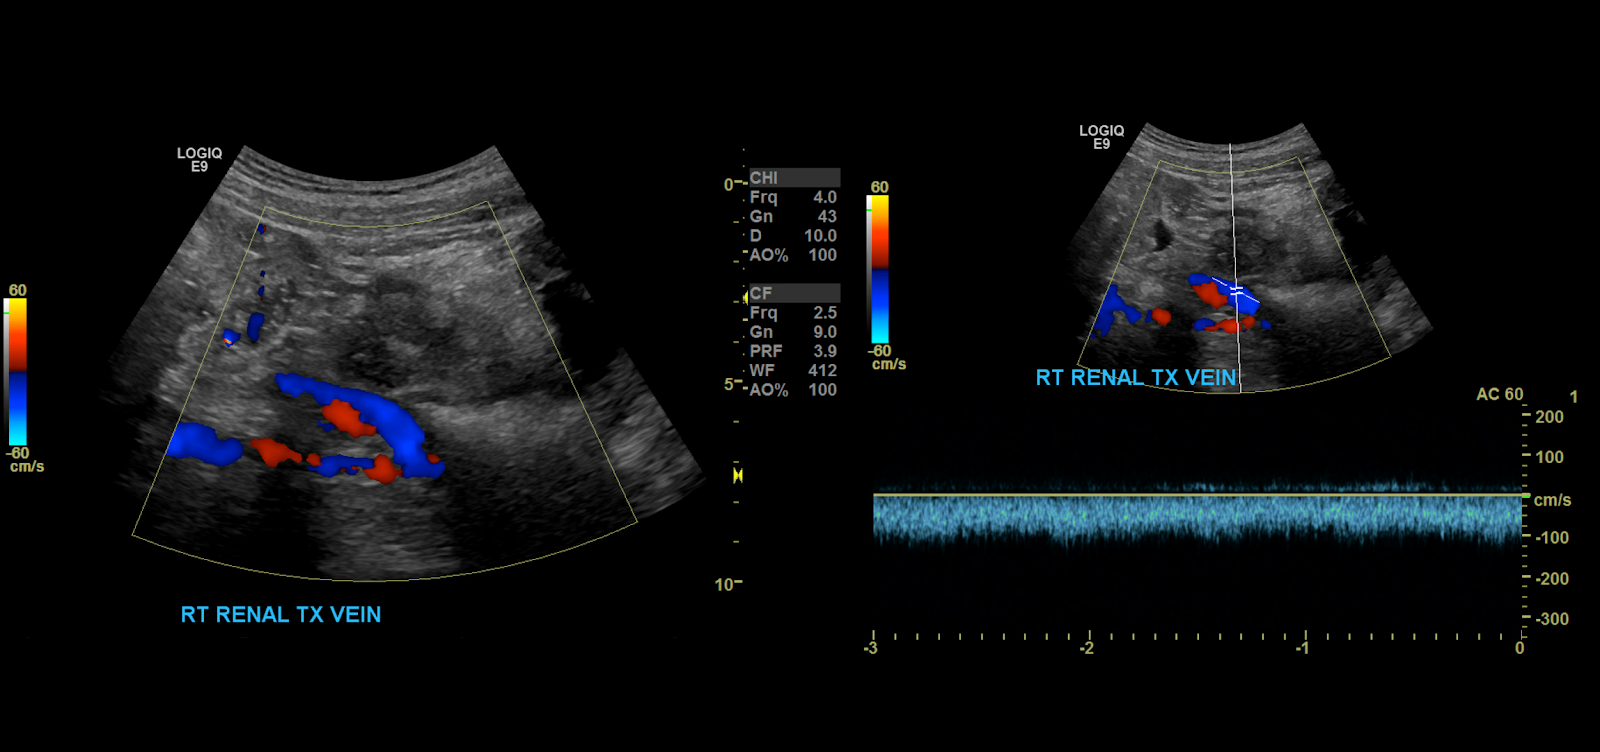

Proceed to doppler the transplant main renal artery and vein. Given the tortuosity sometimes seen in the donor arteries, measuring velocities with angle correction can be tricky. My rule of thumb is that if the artery is perpendicular to the transducer face I don’t use angle correction. If it is parallel to the transducer face I do use angle correction.

Measure the peak systolic and end diastolic velocity. Resistive Index is normally between 0.50 and 0.70. The waveform should be a low resistance waveform with forward flow throughout the cardiac cycle. Take Doppler samples at the anastomosis/proximal section (pay close attention here look for aliasing to detect anastomotic stenosis), the mid and distal portions as well. If there’s any aliasing along the vessel take spectral Doppler samples there too.

Renal Vein